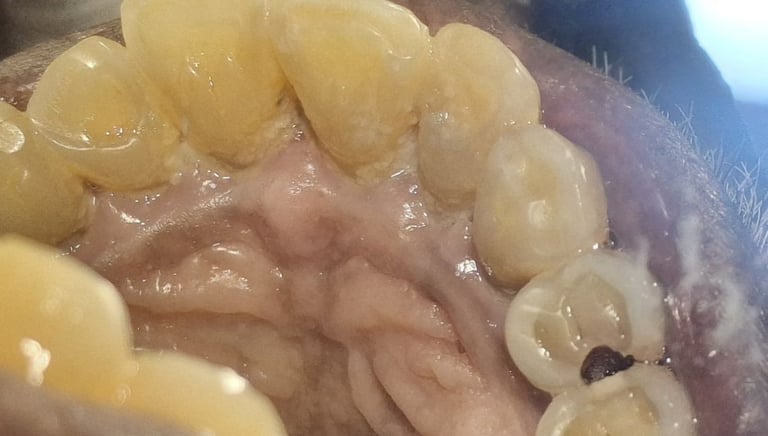

Clinical pictures of teeth requiring RCT

All images are of real cases of teeth where Root canal treatment was performed to remove infection and preserve the natural tooth restoring normal chewing and function of teeth.